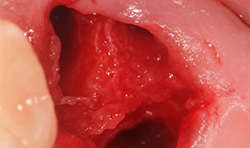

The Magnetic Max (Figs. 1-2) is useful for conservative root extraction.

Fig. 1

Maximum preservation of the alveolar housing and related gingival structures may be achieved following assisted atraumatic tooth extraction by an electrical mallet (Fig. 3).